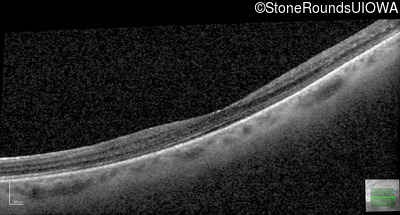

AD Familial Exudative Vitreoretinopathy (IIIE2b)

Age at visit: 32 years

This 32 year old woman has had subnormal acuity (right eye worse than left eye) since very early childhood.

AD Familial Exudative Vitreoretinopathy TSPAN12 Arg50Trp AG(G)>TG(G)   AD